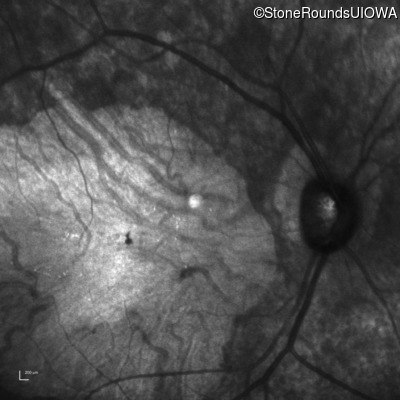

Infrared Fundus Photograph - Right - 10/225 sc

Exemplar